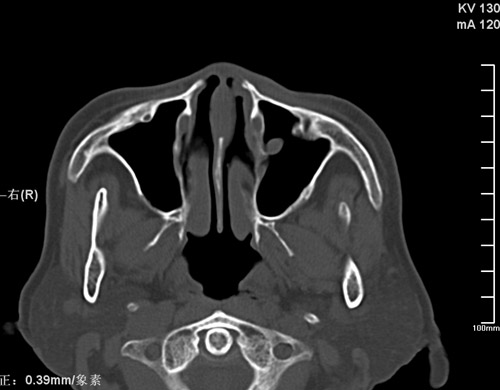

标题: CT17755:女,74 左鼻旁肿胀半年,临床以左上颌窦旁占位行CT [打印本页]

标题: CT17755:女,74 左鼻旁肿胀半年,临床以左上颌窦旁占位行CT

ct考虑鼻前庭囊肿 或鼻翼基底部慢性炎症,左上颌窦少许炎症 请指教

1)考虑左侧鼻前庭囊肿并感染。2)双侧上颌窦炎。

左侧鼻前庭囊肿并感染。双侧上颌窦炎。支持